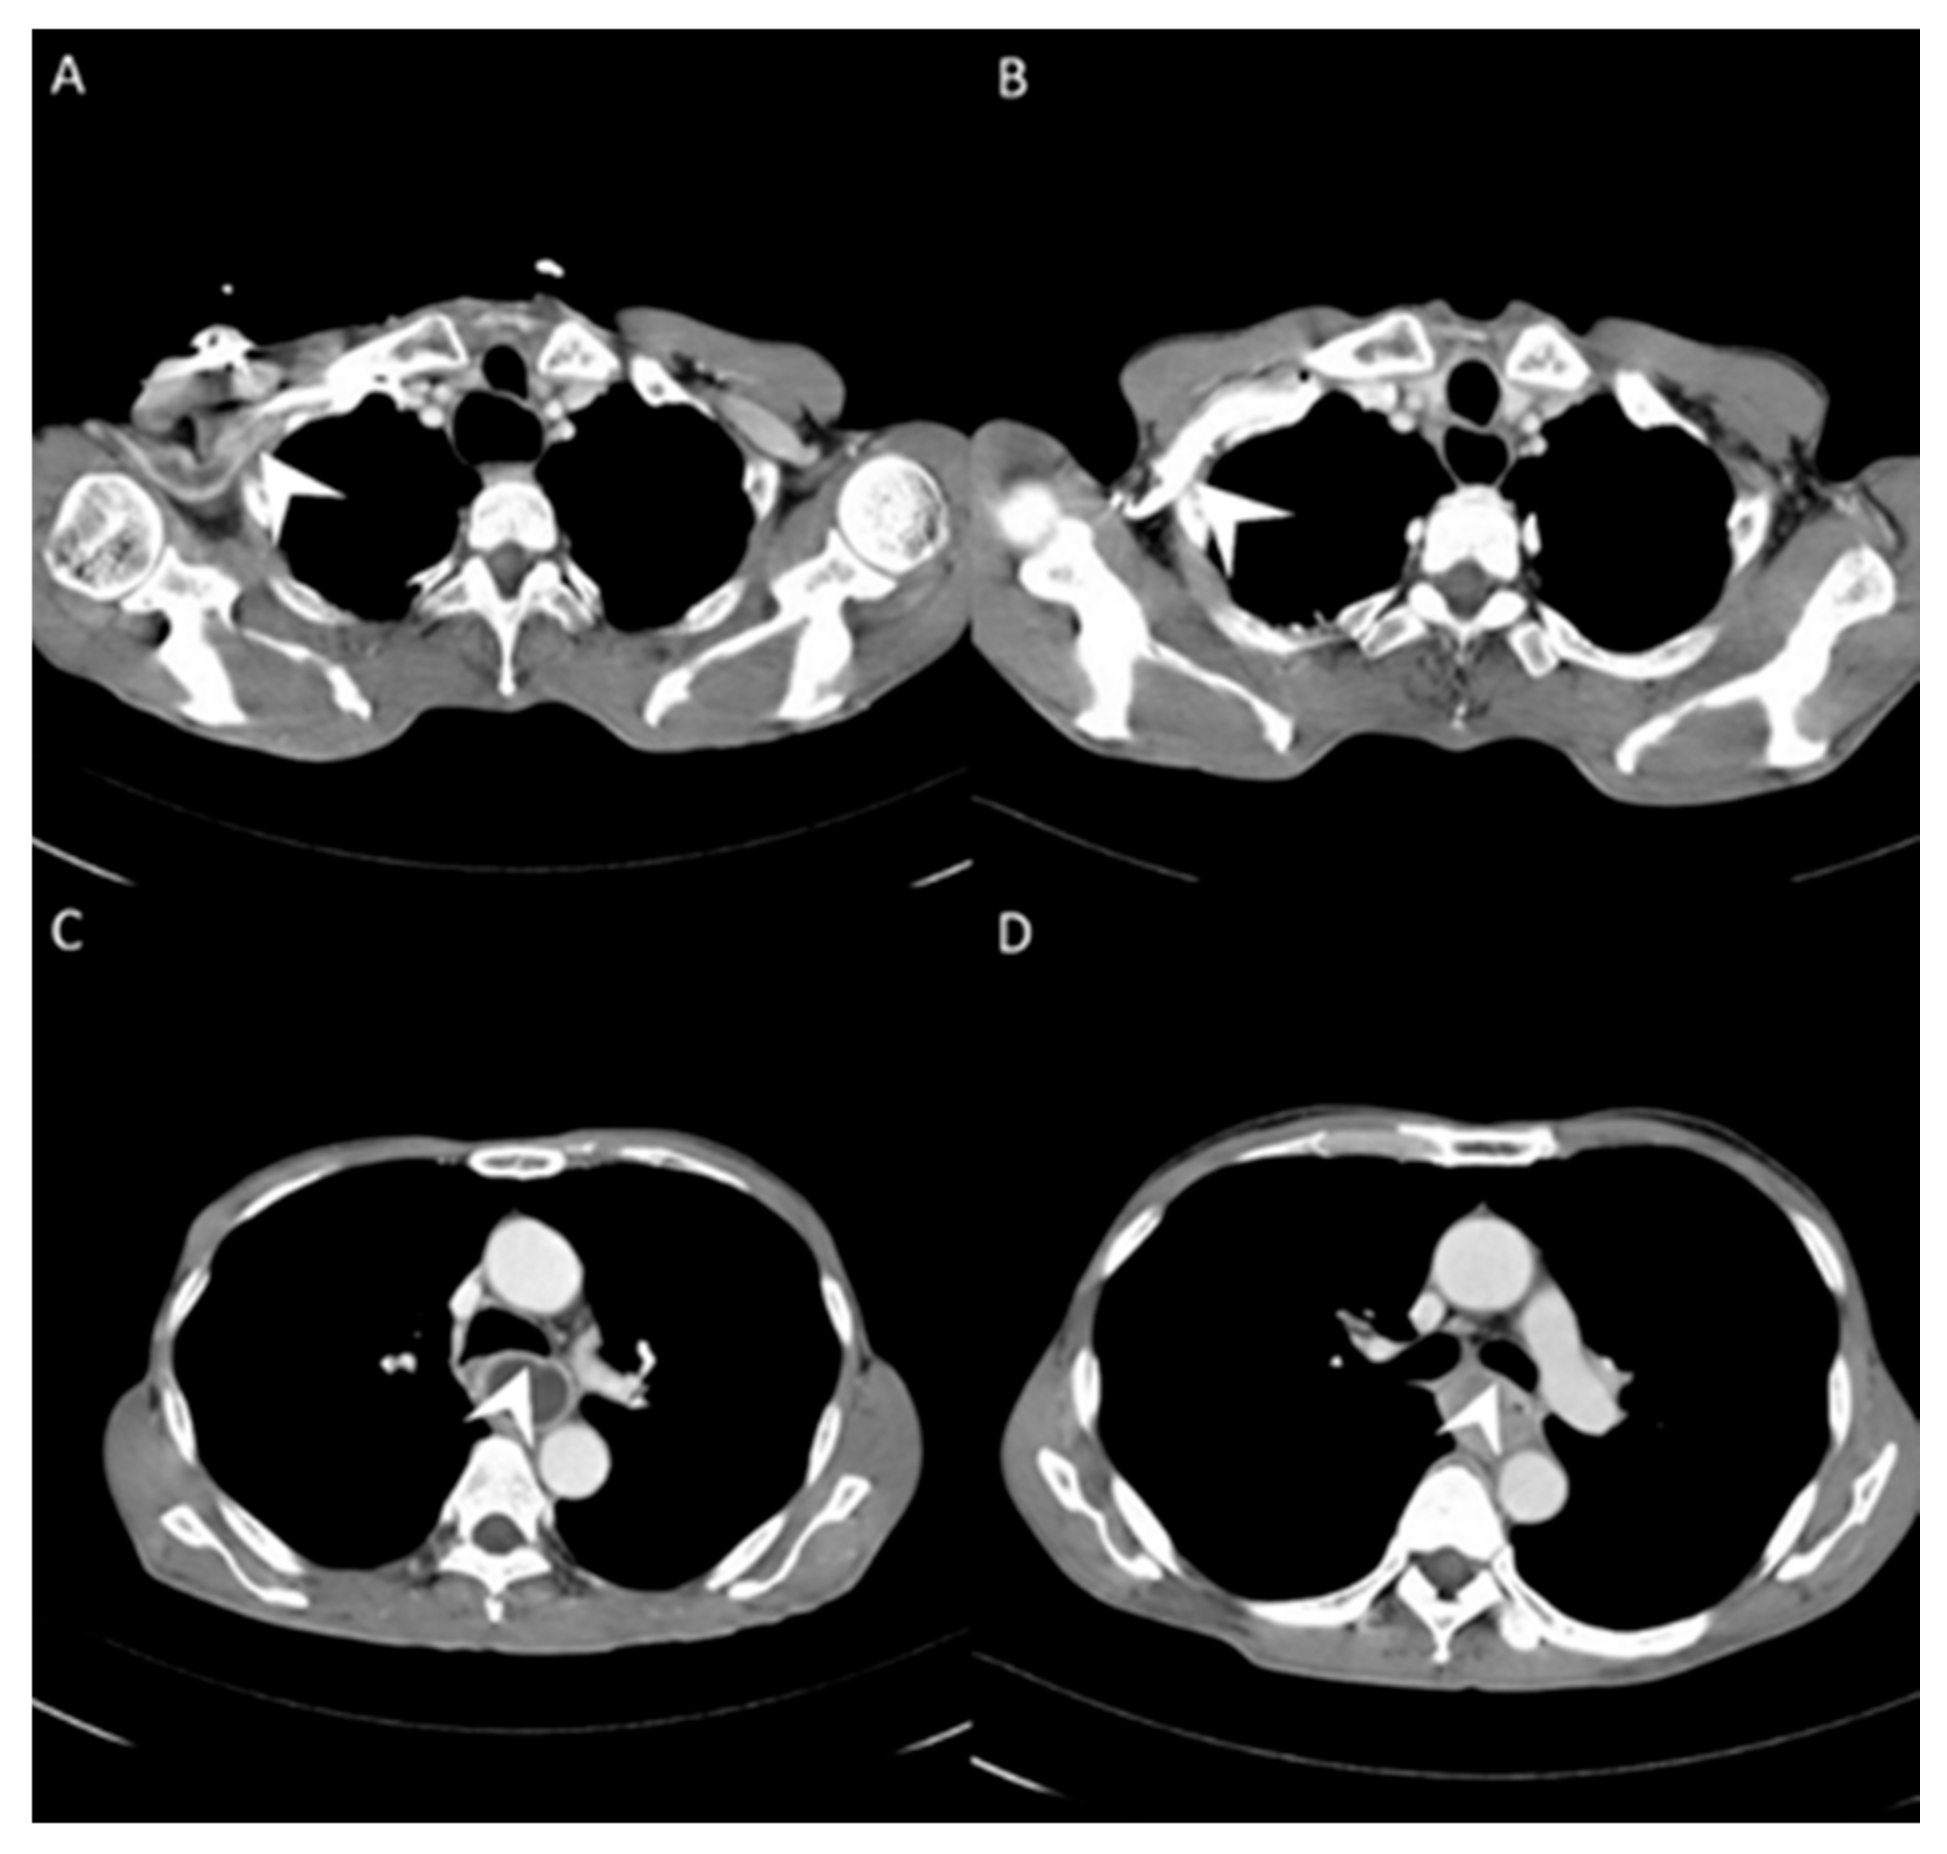

Figure 1.

(A) Less contrast pooling within the subclavian vein (white arrow) was revealed with contrast injected via the power port (central vein). (B) More contrast pooling within the subclavian vein (white arrow) was identified with contrast injected via the peripheral vein. (C) Clear tumor margin (white arrow) was identified with contrast injected via the power port (central vein). (D) Blurred tumor margin (white arrow) with contrast injected via the peripheral vein.

For esophageal cancer patients, disease severity depends on serial imaging surveys including endoscopic ultrasonography (EUS), computed tomography (CT), and positron-emission tomography (PET) [9,10,11,12,13,14,15,16,17,18]. The patients who receive complete tumor resection have a better survival than those with inoperable tumors. Therefore, imaging surveys for tumor invasion to vital structures such as the trachea and descending aorta are crucial to evaluate resectability. All the imaging modalities have limitations that can lead to misinterpretation. EUS is an experience-dependent modality, and fibrotic changes caused by neoadjuvant therapy can make it difficult to evaluate invasion [17,18]. PET is a metabolic survey that can suggest possible distant metastatic lesions but not local tumor invasion. CT is used to clarify local invasiveness; however, the image quality varies according to when the scan is performed and the concentration of the intravascular contrast medium. In addition, CT uses spiral acquisitions that are reconstructed using computer software, and, thus, the image does not represent the actual disease status [19,20]. CT image quality has been correlated with injection flow [21]. A lower injection flow rate means that a longer period of time is required for the contrast medium to enter and become evenly distributed in the circulation, and five to seven whole-body circulations after completing the injection are needed before performing a CT scan. Accordingly, variations exist between the timing of performing a scan, and severe artifacts at the injection site can occur if the image is taken too early, and decreased sharpness can occur if the image is taken too late (Figure 1A,B). A higher injection flow rate means that more contrast medium can enter the circulation in a short time, resulting in a higher immediate concentration without the need to wait. This would then lead to consistency in the image timing and minimize variations in image quality. Theoretically, a central venous contrast medium injection could achieve a higher contrast concentration in a shorter time, and result in better image quality (Figure 1C,D). Moreover, better image quality would enhance the detection of small metastatic lesions and tumor invasion to the surrounding structures. The aim of this study was to analyze and compare the quality and accuracy of CT images obtained after the injection of contrast medium via a power injectable port and those obtained after the injection of contrast medium via a peripheral vein.